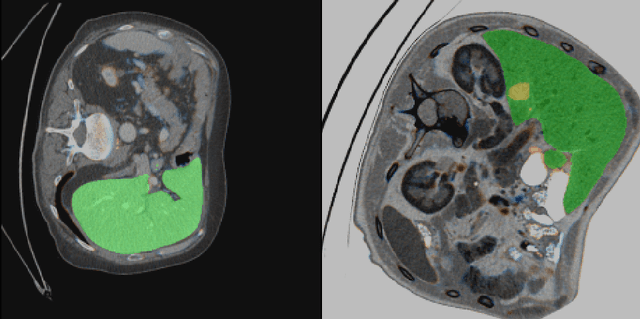

Abstract:Automatic segmentation of hepatic lesions in computed tomography (CT) images is a challenging task to perform due to heterogeneous, diffusive shape of tumors and complex background. To address the problem more and more researchers rely on assistance of deep convolutional neural networks (CNN) with 2D or 3D type architecture that have proven to be effective in a wide range of computer vision tasks, including medical image processing. In this technical report, we carry out research focused on more careful approach to the process of learning rather than on complex architecture of the CNN. We have chosen MICCAI 2017 LiTS dataset for training process and the public 3DIRCADb dataset for validation of our method. The proposed algorithm reached DICE score 78.8% on the 3DIRCADb dataset. The described method was then applied to the 2019 Kidney Tumor Segmentation (KiTS-2019) challenge, where our single submission achieved 96.38% for kidney and 67.38% for tumor Dice scores.